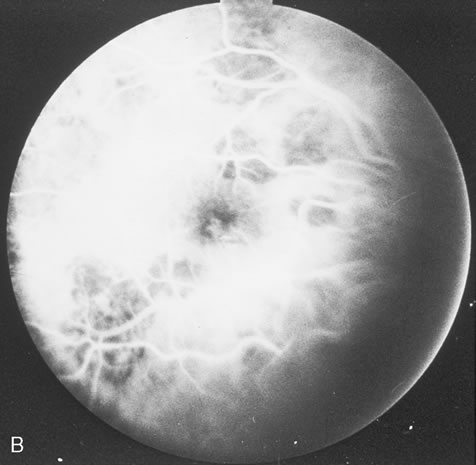

Pneumocystis carinii pneumonia once was the most common presentation of AIDS. It is typically of insidious onset, with features including dry cough, dyspnea, and a diffuse bilateral interstitial infiltrate evident on a chest roentgenogram. Typical multifocal fundus lesions have been described. They are yellow-white and have a characteristic pattern on fluorescein angiography (Fig. 10A, 10B, and 10C). Diagnosis is made by demonstrating the protozoon via sputum induction, bronchioalveolar lavage, and transbronchial or open-lung biopsies. Treatment modalities include trimethoprim-sulfamethoxazole (TMP-SMX).31

Fig. 10. A. The retinal involvement of Pneumocystis carinii is manifested by multifocal, yellow-white lesions. B and C. On fluorescein angiography, the lesions fail to delineate in the early phase (B) but stain in the late phase (C).